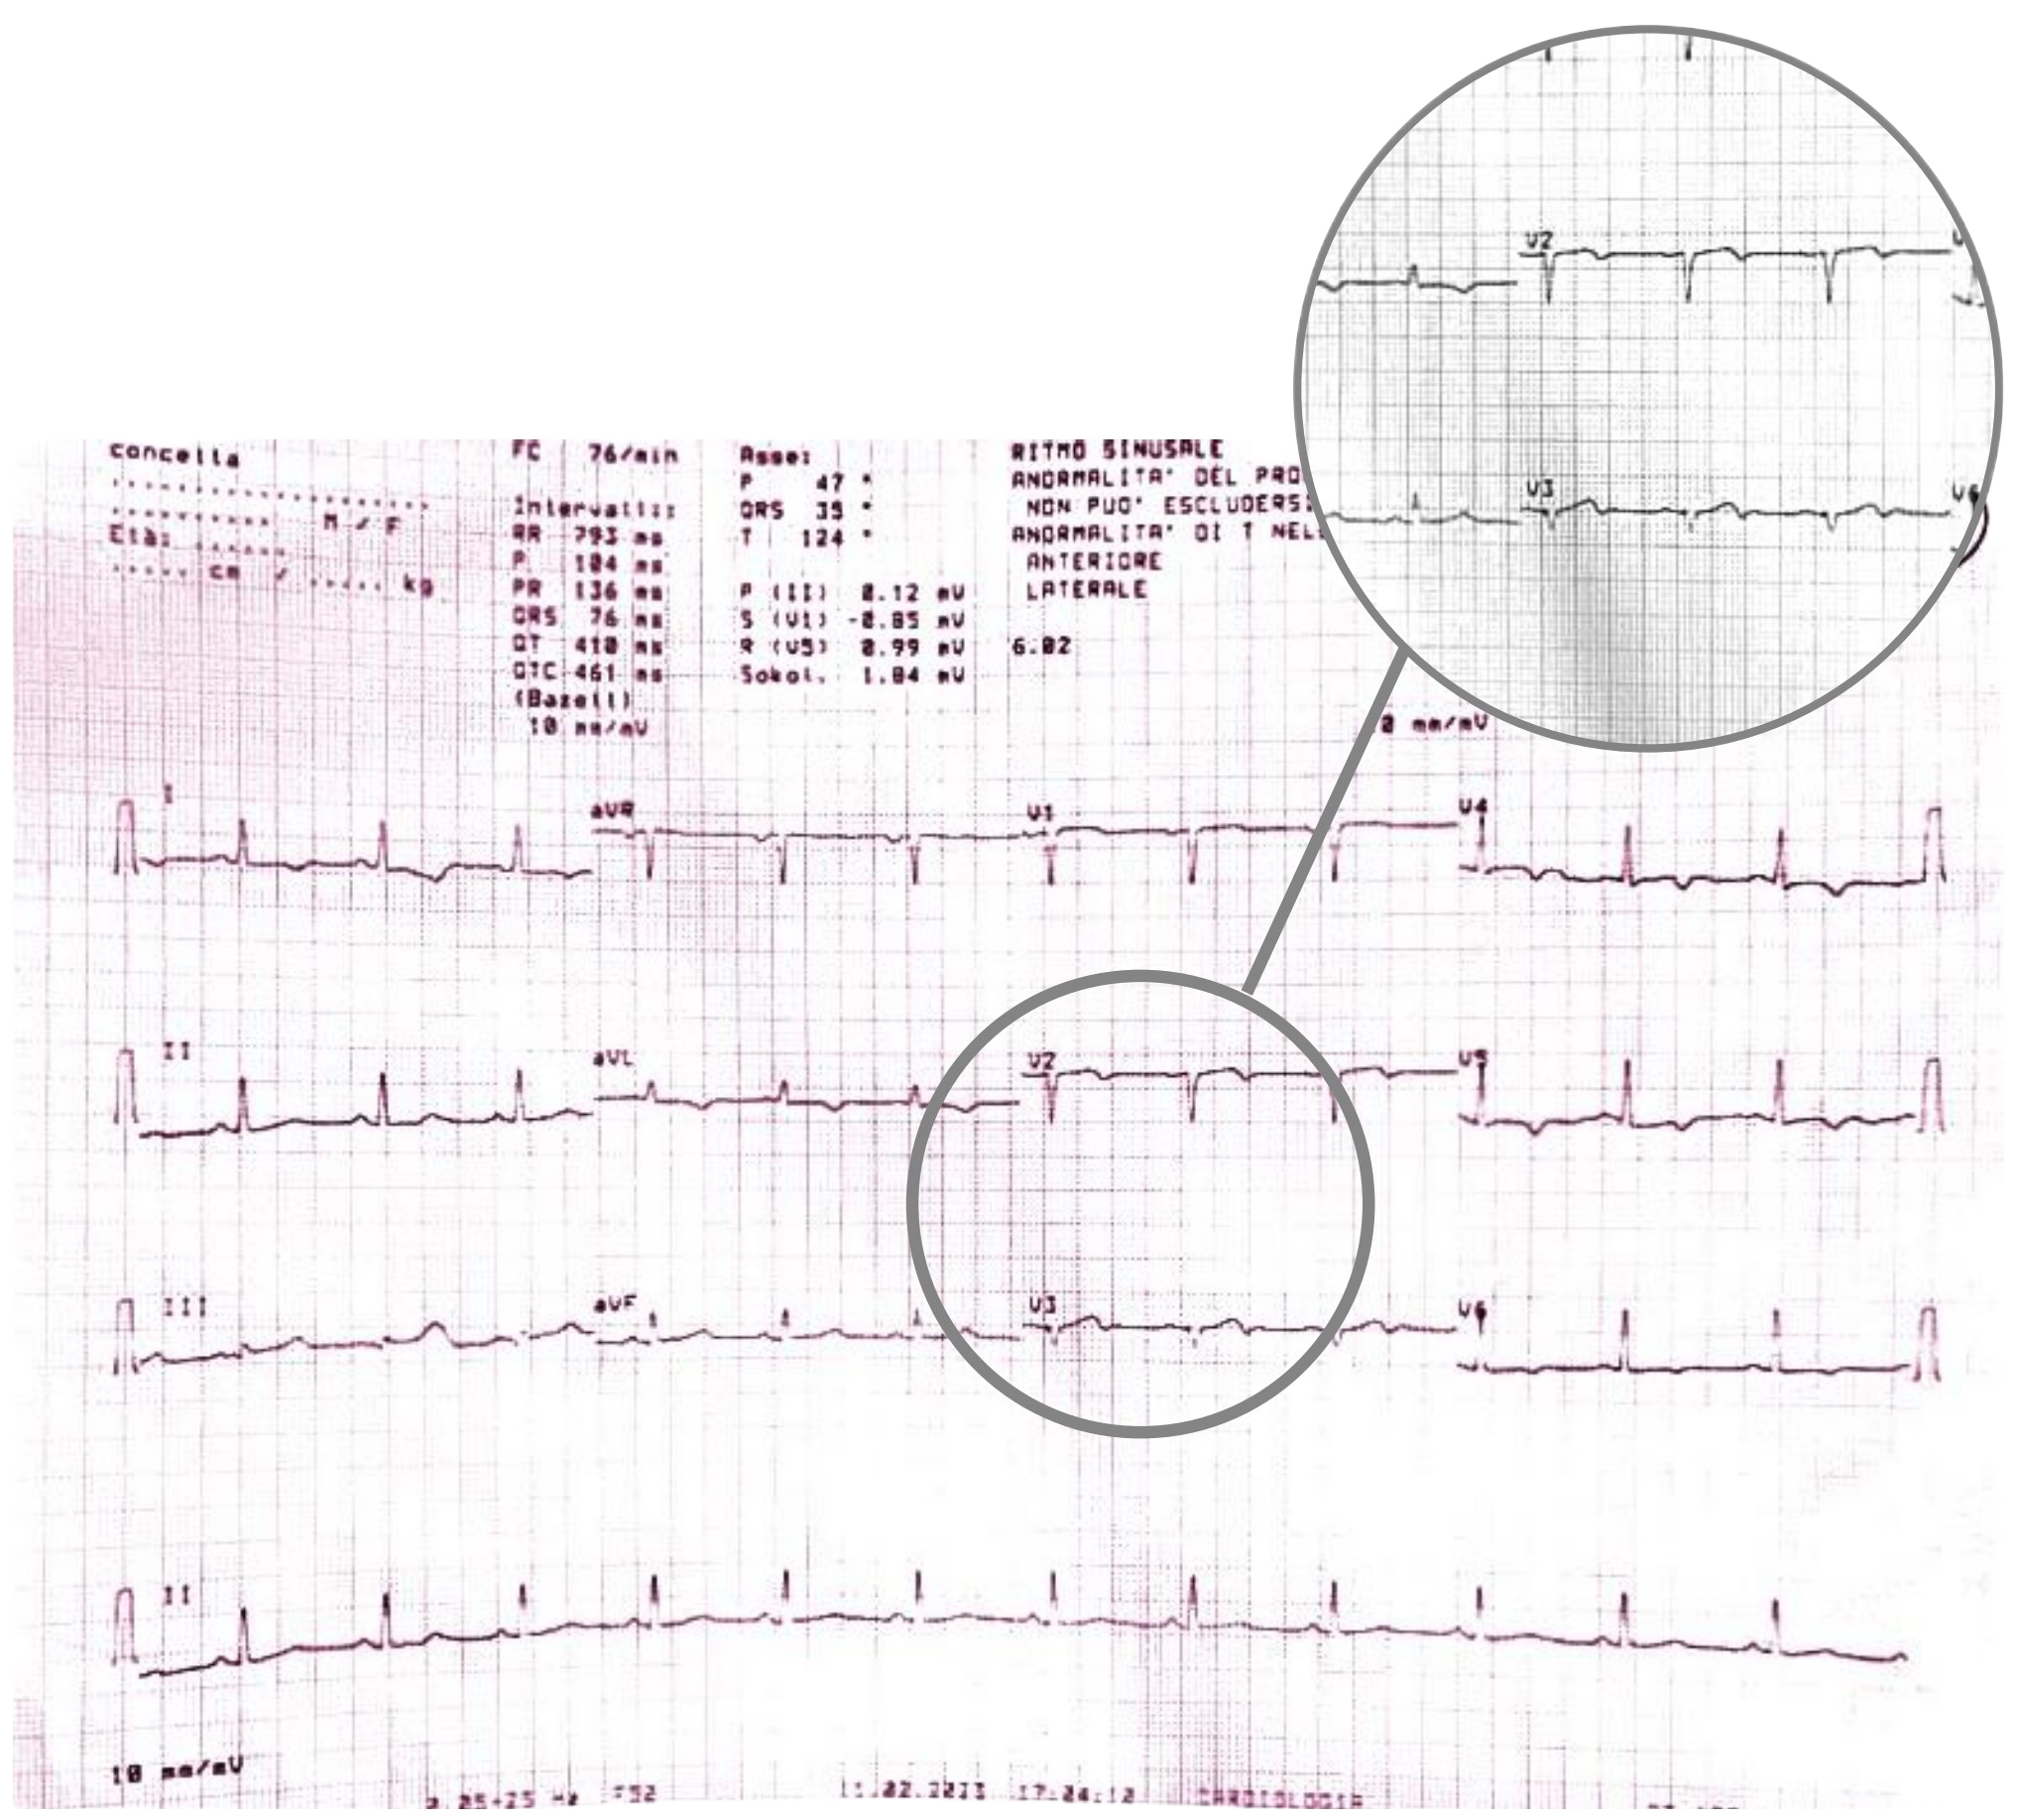

During the hospitalization, the patient experienced the recurrence of similar episodes of mild chest pain; all of them occurred after minor exertion, lasted a few minutes and were self-resolving. The 12 leads ECG performed during the last one of them showed few changes: biphasic T waves with initial positivity and terminal negativity in leads V2 and V3 slightly resembling type A Wellens pattern were present (Fig. 4 — ECG).

Fig. 4.

Fig. 4.ECG showing biphasic T waves with initial positivity and terminal negativity in leads V2 and V3 slightly resembling type A Wellens Syndrome. ECG, electrocardiogram.